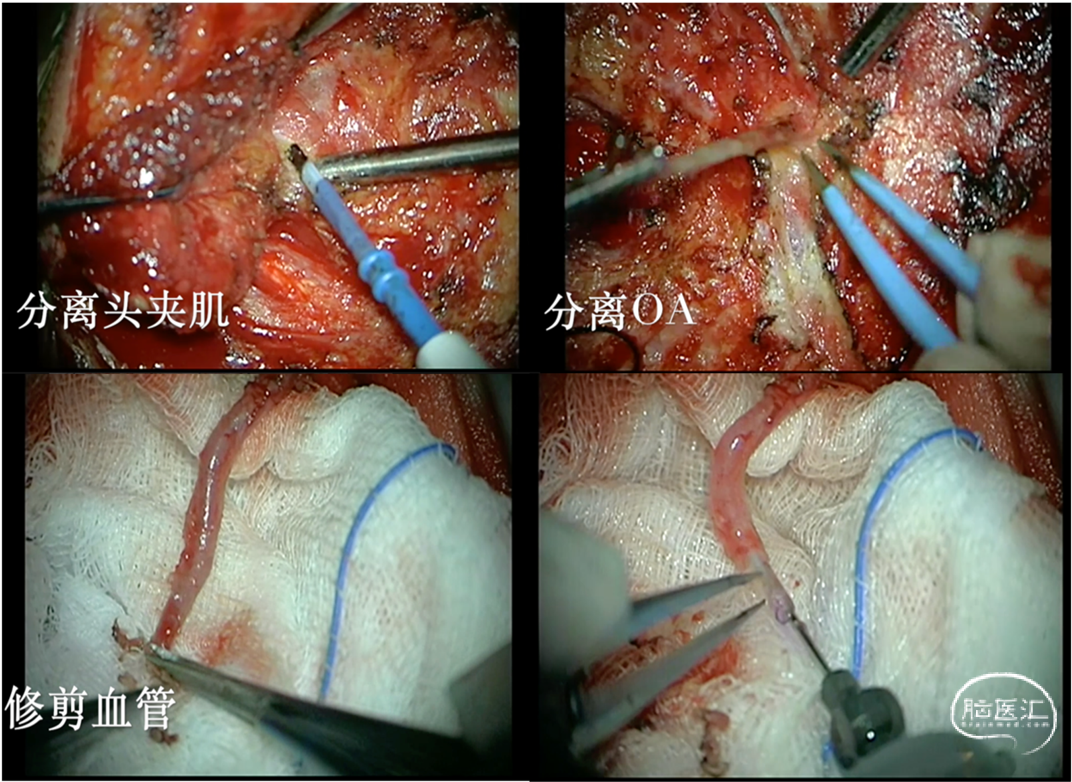

1.取侧俯卧位,远外侧入路,于头夹肌与头最长肌之间分离枕动脉OA,修剪血管残端,准备搭桥(图4)。

图4.手术中分离头夹肌,并从头夹肌与头最长肌之间剥离OA,同时修剪备用。